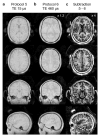

Magnetic Resonance Imaging (MRI) scanners produce loud acoustic noise originating from vibrational Lorentz forces induced by rapidly changing currents in the magnetic field gradient coils. Using zero echo time (ZTE) MRI pulse sequences, gradient switching can be reduced to a minimum, which enables near silent operation.Besides silent MRI, ZTE offers further interesting characteristics, including a nominal echo time of TE = 0 (thus capturing short-lived signals from MR tissues which are otherwise MR-invisible), 3D radial sampling (providing motion robustness), and ultra-short repetition times (providing fast and efficient scanning).In this work we describe the main concepts behind ZTE imaging with a focus on conceptual understanding of the imaging sequences, relevant acquisition parameters, commonly observed image artefacts, and image contrasts. We will further describe a range of methods for anatomical and functional neuroimaging, together with recommendations for successful implementation.